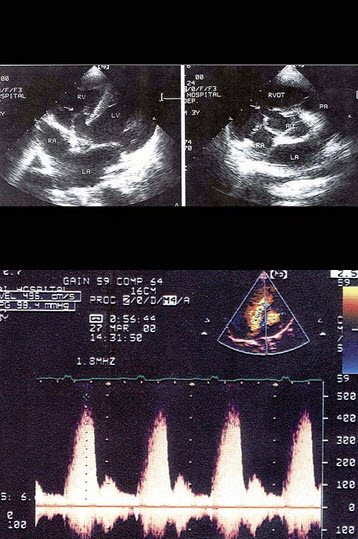

51、单项选择题

患者老慢支疾病多年,该病例最有可能诊断()

A.原发性肺动脉扩张

B.右流增宽

C.肺动脉瓣关闭不全

D.肺动脉高压

E.动脉导管未闭